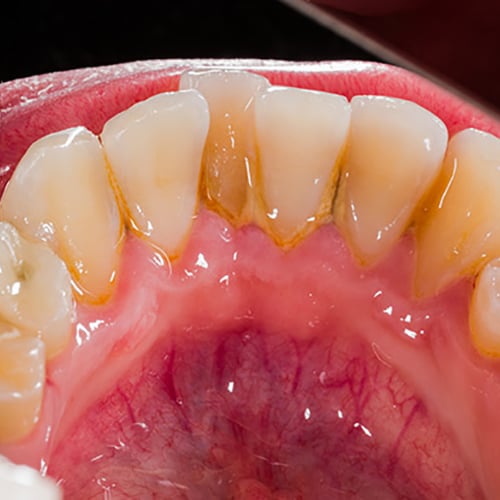

Supragingival Calculus

Gingival Inflammation: Scaling | Colgate® Professional

Before and after photos of a patient who has heavy scaling in the mouth, gingival inflammation. Prevent health issues by practicing better oral health. -